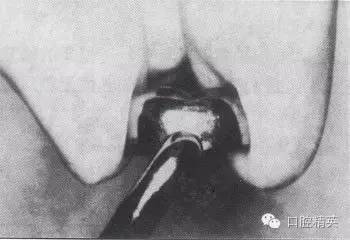

d.修整冠外形

金屬預(yù)成冠修復(fù)-兒童乳牙